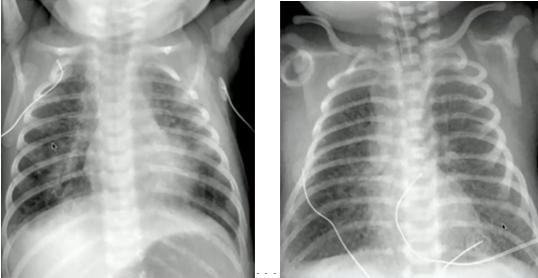

Example 2 主诉:足月儿剖宫产出生后出现呼吸困难。

胸片特点:沿肺门分布的白色线状阴影;间质/肺裂增粗;卧位左侧胸膜增厚:少量胸腔积液(不表现为肋膈角变钝)。

诊断:新生儿暂时性呼吸增快症(新生儿湿肺):生后肺内液体过多引起暂时性呼吸困难,1~2天后自然好转;常见于剖宫产或短顺产产程的足月儿,多见于男婴。

图6.新生儿暂时性呼吸增快症(左:生后胸片;右:生后20小时胸片)